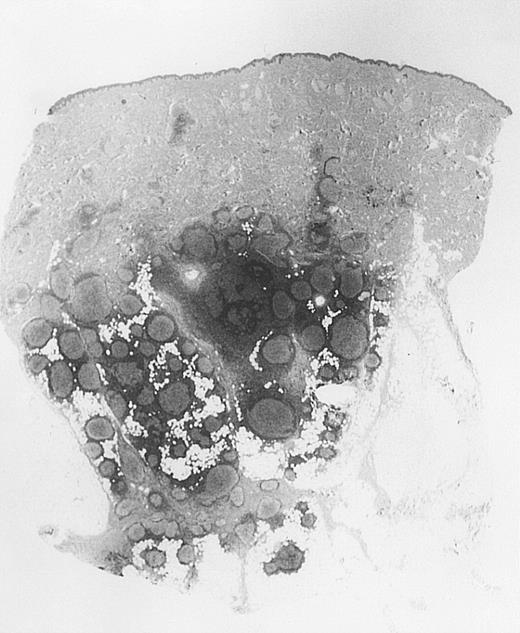

All cases of follicular lymphoma were classified as grade 2 according to the REAL classification. Histology showed bottom-heavy lymphoid infiltrates with prominent follicular pattern (Figures3 and 4). A well-formed mantle zone around most follicles was present only in 2 patients. In the other specimens the mantle zone was either reduced (11 patients) or nearly absent (2 patients) (Figure5). A clear-cut marginal zone was never observed. Tingible body macrophages within follicles were present only in 1 patient and were absent in the other 14 patients. Cytomorphology of follicles in all patients showed variable proportions of centrocytes (cleaved follicle center cells) and centroblasts (Figure6). The interfollicular areas revealed the presence of small lymphocytes and histiocytes admixed with a few larger cells and occasionally other inflammatory cells such as eosinophils and plasma cells.

Bottom-heavy lymphoid infiltrate with prominent follicular pattern.

Located in the deep dermis and subcutaneous tissue (patient 9).

Dense infiltrate with prominent follicular pattern.

Appears within the entire dermis (patient 5).

Neoplastic follicles.

The follicles lack a normal mantle zone and reveal nearly complete absence of tingible body macrophages (patient 9).

Cytomorphology.

Centroblasts and centrocytes evident within a follicle (patient 3).